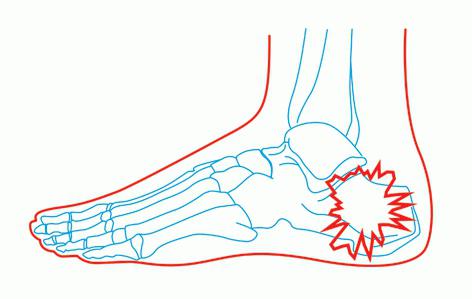

Основные симптомы перелома пятки

- Острая и резкая боль в месте повреждения.

- Невозможность наступить на стопу.

- Заметная деформация нижней конечности.

- Отёчность и расширение в области пятки.

- Присутствие кровоподтёков на подошве стопы.

При появлении таких опасных симптомов следует незамедлительно обращаться к профессиональным и квалифицированным специалистам. Доктор проведёт обследование больного с применением рентгена. И только после выявления всех особенностей ситуации и стадии развития повреждения специалист составляет оптимальный план лечения с последующим курсом реабилитации. Пренебрежение такими мероприятиями приведёт к усугублению ситуации, а также значительно повышает вероятность развития осложнений. Обратиться за качественной реабилитацией вы всегда можете к дипломированным специалистам нашего современного центра восстановления «Исток».